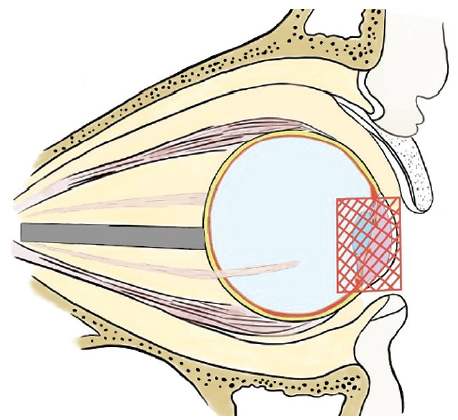

Fig. 16. Installation of an external cosmetic prosthesis after globe removal using the evisceration method with removal of the cornea. The external cosmetic prosthesis is congruent with the surface of the endoprosthesis; there is no liquid or air vacuoles between them

Рис. 16. Установка наружного косметического протеза после удаления глазного яблока методом эвисцерации с удалением роговицы. Наружный косметический протез конгруэнтен поверхности эндопротеза, между ними отсутствует жидкость или вакуоли воздуха

Fig. 17. MSCT of the orbit, axial section, soft tissue reconstruction mode. The state after endoprosthesis installation after evisceration of the right globe. In the anterior part of the right orbit, a centrally located endoprosthesis is visualized (red arrow), round in shape, with homogeneous structure, 20 mm in diameter, with an average density of +372 HU, no additional inclusions in the area of the prosthesis were identified, the endoprosthesis capsule with clear, even contours is visualized in the anterior part. An external cosmetic prosthesis is adjacent to the front surface of the endoprosthesis (green arrow). The orbital floor of the right orbit is reconstructed with a mesh implant, without any signs of bone-destructive changes

Рис. 17. МСКТ орбиты, аксиальный срез, режим мягкотканной реконструкции. Состояние после эндопротезирования правого глазного яблока после эвисцерации. В переднем отделе правой орбиты визуализируется центрально расположенный эндопротез (красная стрелка), округлой формы, однородной структуры, диаметром 20 мм, средней плотностью +372 HU, дополнительных включений в области протеза не выявлено, в передней части визуализируется капсула эндопротеза с чёткими ровными контурами. К передней поверхности эндопротеза прилежит наружный косметический протез (зелёная стрелка). Нижняя стенка правой орбиты протезирована сетчатым имплантатом, без признаков костно-деструктивных изменений